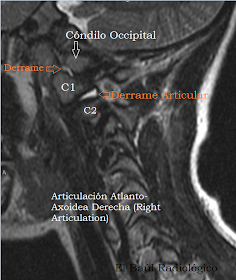

FIGURA 6) Imagen FSE-T2 en la que se observa el derrame articular en la articulación, cóndilo-atlas pero especialmente en la Atlanto-Axoidea lateral derecha. Recuerda al bloqueo articular, con derrame, que se observa en la articulación de la rodilla depués de un traumatismo que provoca sinovitis.